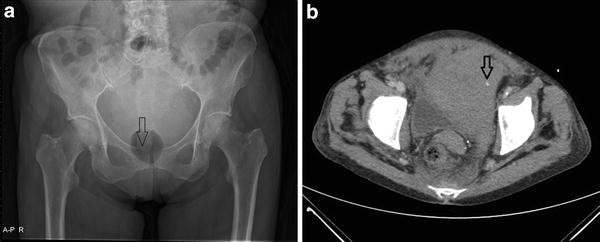

A D This Patient Was Admitted In Shock After Blunt Abdominal Trauma A Download Scientific Diagram

A D This Patient Was Admitted In Preshock After A Blunt Impact In The Download Scientific Diagram